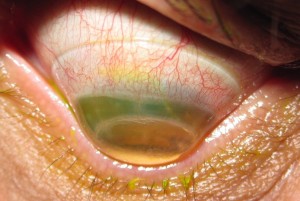

Esta semana quiero comentar este estudio cuyo propósito fué investigar las tasas de éxito y fracaso de la adaptación de la lente escleral en el queratocono grave. Para ello se diseño un estudio de series de casos retrospectivos.

Se propuso la adaptación de lentes esclerales para los 75 ojos incluidos en el estudio. Ocho ojos se sometieron a una cirugía de trasplante debido a la agudeza visual insuficiente con las lentes, intolerancia a los lentes y problemas con el manejo de los lentes. Doce ojos no fueron adaptados debido a la buena agudeza visual en el otro ojo o una contraindicación para el uso de lentes. Tres ojos se adaptaron con éxito con lentes corneales o híbridas. Se prescribieron lentes esclerales en 51 de 75 ojos. La ganancia media en la agudeza visual (lente versus agudeza visual corregida con gafas) fue de 0.54 ± 0.18 (fracción decimal, optotipo Snellen). Siete ojos se perdieron durante el seguimiento, cuatro ojos abandonaron el uso de la lente escleral debido a la incapacidad para manejar las lentes, y cuarenta ojos usaron las lentes en su última visita de seguimiento, con un intervalo de seguimiento promedio de 30.15 ± 12.83 meses.

En conclusión, cuarenta de los 51 ojos con queratocono grave que de otra forma se habrían sometido a cirugía de trasplante se trataron con éxito con el uso de lentes esclerales a largo plazo. De esta manera, la indicación de queratoplastia se redujo a menos de la mitad en esta población de queratocono. Hoy en día, y siempre que no haya una evolución del Queratocono, la lente escleral es una excelente opción de tratamiento.